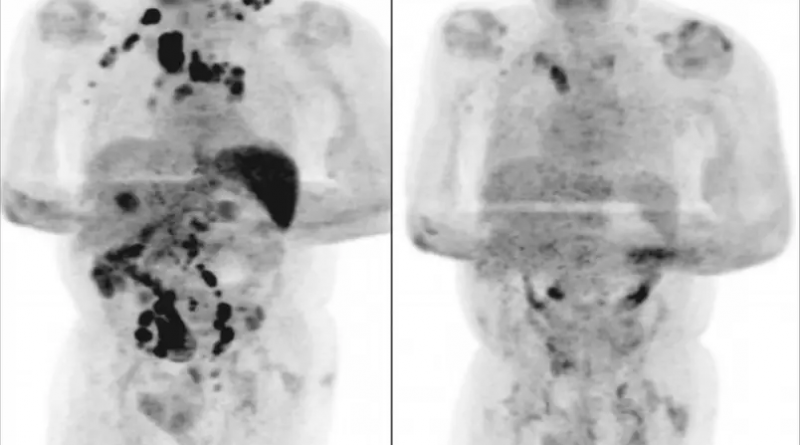

Um homem de 61 anos, diagnosticado com linfoma de Hodgkin em estágio III, teve remissão generalizada da doença após contrair a Covid-19. O caso foi publicado no periódico médico British Journal of Hematology.

De acordo com os cientistas, o idoso ficou em tratamento por 11 dias e foi liberado para finalizar a recuperação da Covid-19 em casa. Não foram administrados corticosteroides ou imunoquimioterapia, medicamentos usados no tratamento do linfoma. Quatro meses depois, os médicos, no entanto, afirmaram que o inchaço dos nódulos havia diminuído e um exame de tomografia revelou a remissão generalizada do linfoma.

A hipótese levantada pelos autores do artigo é de que a infecção pelo novo coronavírus desencadeou uma resposta imune contra o tumor. A publicação ainda afirma que casos de remissão espontânea já haviam sido descritos, porém com outras infecções de pneumonia infecciosa e no contexto do linfoma não Hodgkin de alto grau.